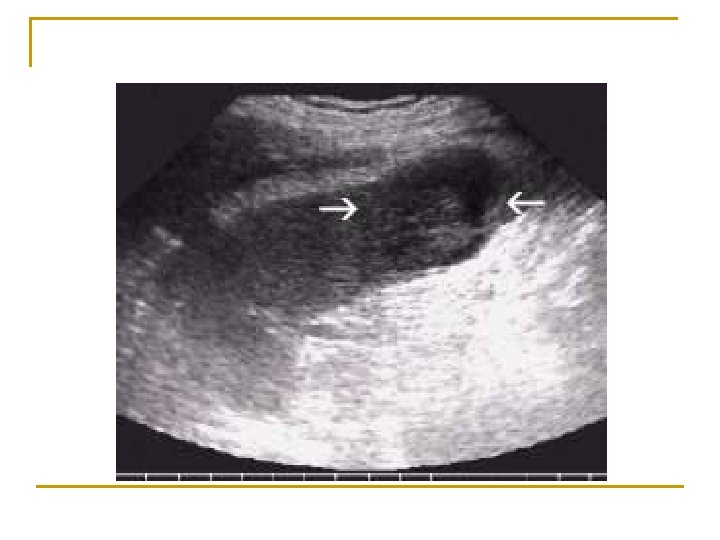

n n n Tanı: Tanı USG (safra kesesi duvarında >2 mm’lik kalınlaşma, perikolesistik sıvı, intramural gaz, kanallarda dilatasyon; sonografik Murphy pozitifliği) HIDA sintigrafisi, BT Tedavi: Tedavi I. V sıvı + GİS istirahati + parenteral analjezik + antibiyoterapi (komplike olgular, ağır seyir, immünsüpresyon, yaşlı, sarılık) + kolesistektomi/kolesistotomi Komplikasyon (%10 -15): hepatik, karın içi apse, safra kesesi nekrozu, gangreni, perforasyonu